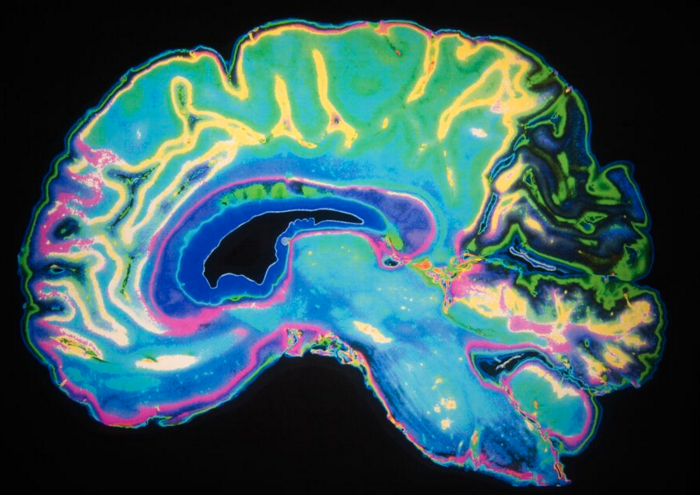

Where Do We Stand in the Clinical Care of Alzheimer's Disease?

The two major barriers to Alzheimer’s research are money and participation.